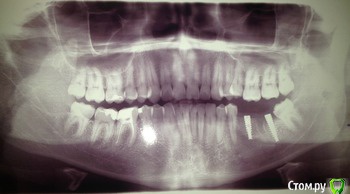

red_butler Опубликовано 18 июля, 2016 Поделиться Опубликовано 18 июля, 2016 обращался говорит все нормально, но как может быть нормально если ноет. http://s014.radikal.ru/i327/1607/a3/1d09b7648e0a.pngнет, это не нормально, нужен очный осмотр, есть вопросы по дальнему импланту. Ссылка на комментарий

red_butler Опубликовано 18 июля, 2016 Поделиться Опубликовано 18 июля, 2016 http://s019.radikal.ru/i618/1607/48/52dc3ac3201d.jpgзуб мудрости удалить, в области дальнего импланта резорбция кости, плюс просвечивает заглушка.Покажитесь еже раз своему врачу Ссылка на комментарий

dok1 Опубликовано 19 июля, 2016 Поделиться Опубликовано 19 июля, 2016 Когда нибудь зуб мудрости " натворит делов " и протезирование на имплантах можно считать не состоятельным. Дальний имплант незаглублен до нужного уровня. И паралел нее ближнему желательно бы его поставить. Таким образом можно уйти на винтовую фиксацию от цементной. У дальнего импланта микрорезьба скорее всего ифицирована, верхний срез импланта на снимке в идеале должен быть вровень с окружающей костью. Ссылка на комментарий

rivezico Опубликовано 22 июля, 2016 Поделиться Опубликовано 22 июля, 2016 Незаглублены, судя по снимку, оба винта. Можно подробней что может натворить зуб мудрости имхо зуб надо было удалить что значит микрорезьба инфицирована? инфицирование имплантата. такое может быть в Вашем случае, хотя не факт. то что прорезалась заглушка - плохо. Ссылка на комментарий